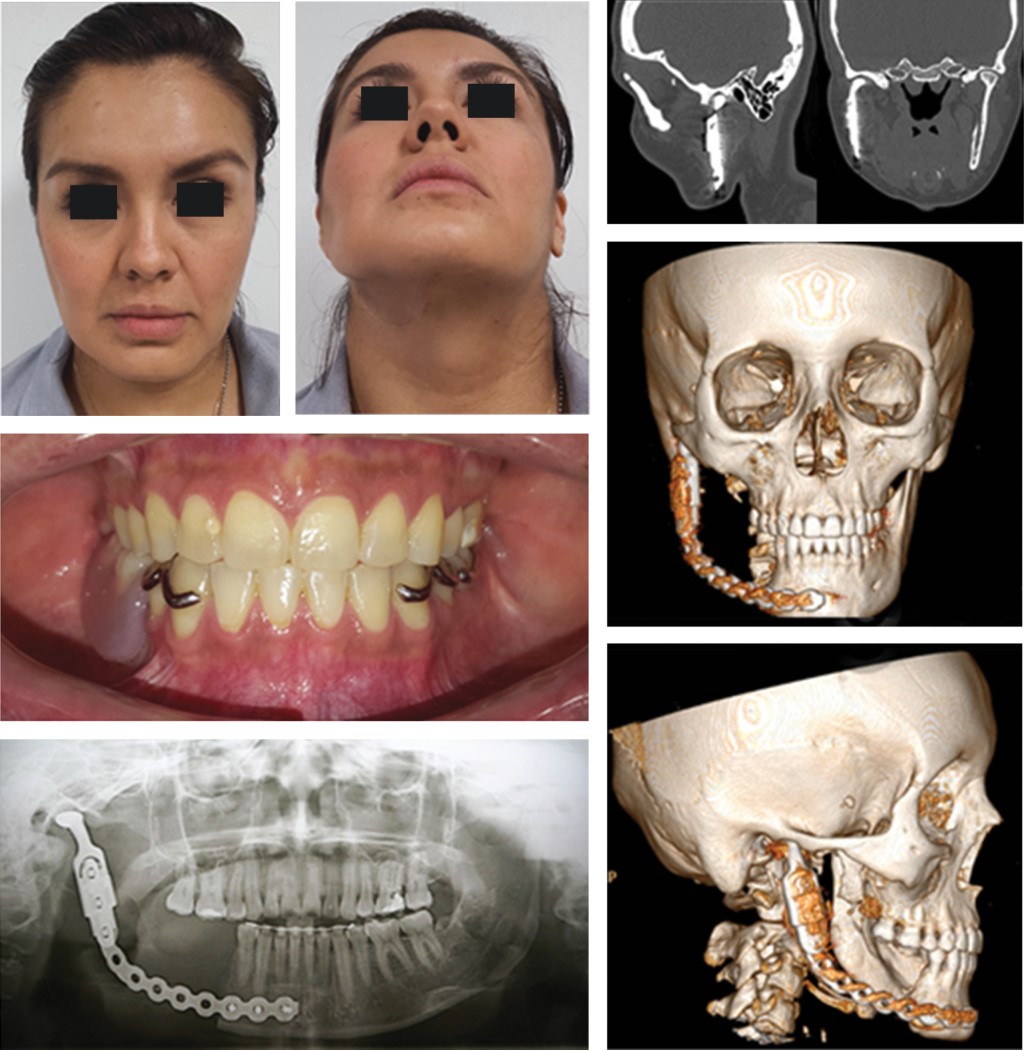

En la tomografía computarizada simple en cortes axiales, coronales y sagitales y reconstrucciones multiplanares en tercera dimensión se observa lesión osteolítica expansiva con infiltración en la totalidad en el cuerpo, rama mandibular, cóndilo y apófisis coronoides del lado derecho, heterogénea de bordes mal delimitados con efecto de volumen en la región (Figura 1).

Previo protocolo de asepsia y antisepsia y posterior colocación de campos estériles, entra paciente a sala en decúbito dorsal, bajo anestesia general balanceada por intubación orotraqueal se procede a realizar infiltración en región submandibular derecha, a base de lidocaína al 2% con epinefrina al 1 × 100,000 con fines hemostáticos y de hidrosección, se inicia abordaje submandibular derecho tipo Risdon con extensión a región submentoniana para después efectuar disección por planos hasta encontrar plano óseo, se realiza marcaje de osteotomía determinando 1 cm de margen libre de lesión a nivel de segundo premolar inferior derecho, posteriormente se efectúa disección de elementos vasculares y nerviosos de la región mandibular para efectuar resección en bloque de cuerpo y rama mandibular del lado derecho. Por último se procede a colocar y adaptar placa de reconstrucción sistema 2.4, con aditamento condilar derecho, previamente conformada con estudio de estereolitografía, se fijan tres tornillos bicorticales sistema 2.4 en borde basal mandibular, posteriormente al observar adecuada estabilidad, se procede a cierre por planos y posterior cierre de piel con sutura subdérmica, concluyendo procedimiento quirúrgico sin complicaciones (Figuras 2 y 3).

Figura 1

Figura 2

Figura 3